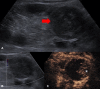

The introduction of ultrasound contrast agents has rendered contrast-enhanced ultrasound (CEUS) a valuable complementary technique to address clinically significant problems. This pictorial review describes the use of CEUS guidance in abdominal intervention and illustrates such application for a range of clinical indications. Clinical application of CEUS discussed include commonly performed abdominal interventional procedures, such as biopsy, drainage, nephrostomy, biliary intervention, abdominal tumor ablation and its subsequent monitoring, and imaging of vascular complications following abdominal intervention. The purpose of this article is to further familiarize readers with the application of CEUS, particularly its specific strength over alternative imaging modalities, in abdominal intervention.